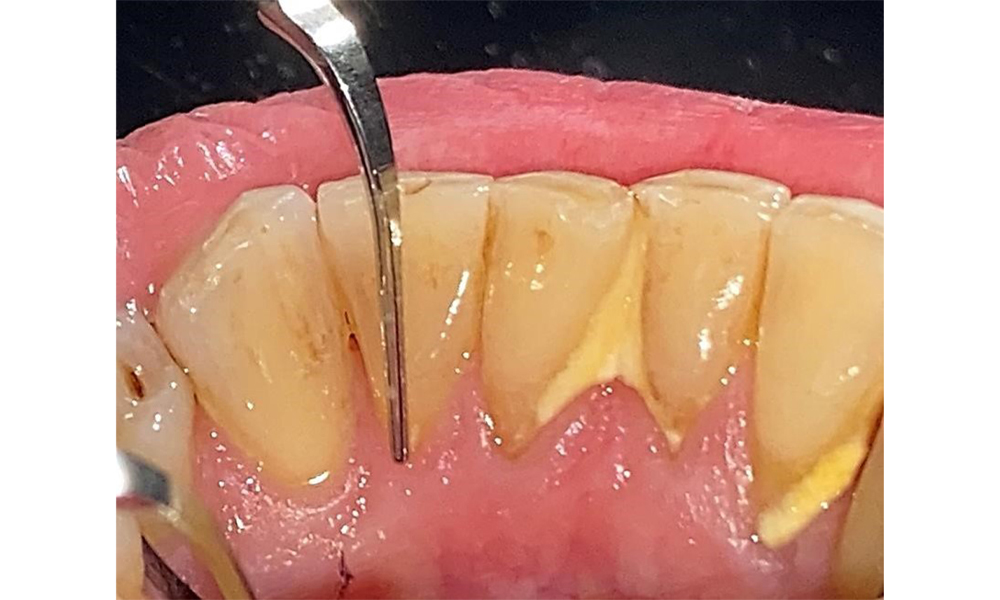

The patient has stage II, grade B periodontitis (5). At 1 to 3 mm, the clinical probing depths were within the physiological range. Localized probing depths of 5 mm were observed on the mesiopalatal aspects on both 17 and 27. There are generalized recessions of 1–3 mm with partial loss of the interdental papillae (Fig. 2, Fig. 3, Fig. 4)

The documentation of periodontal findings, including pocket depth probing and bleeding status, is mandatory during each dental appointment due to the presence of periodontitis (Fig. 8). This will record the individual therapeutic needs and facilitate a rapid response to any progression of the pre-existing periodontitis.